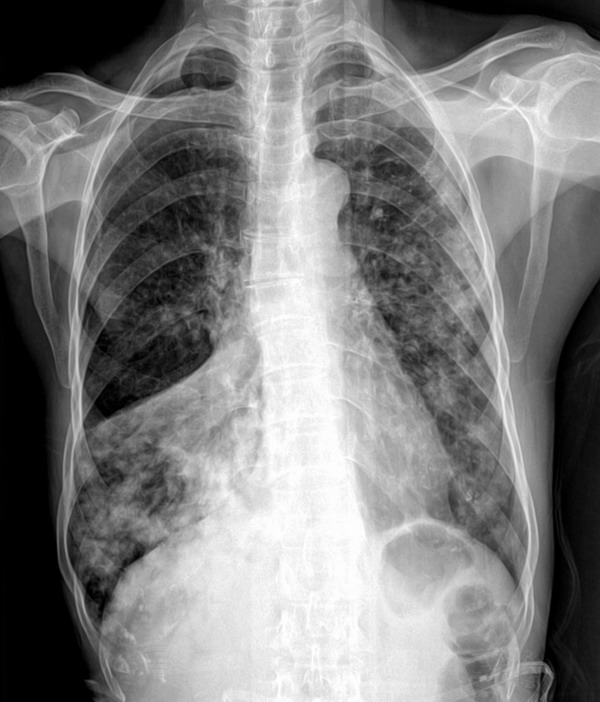

f 70y 咳嗽 气喘!

右肺中叶不张,原因? 确诊为肺ca (刚知道的)

右中叶不张,双肺多发结节影,考虑右中心性肺癌伴双肺转移。

双肺野均可见呈弥漫分布结节状略高密度影,以右下肺及左肺为多,边界不清;于右下肺野内见“倒三角形”高密度区。

1、考虑右肺中心型肺ca伴右肺中叶阻塞性炎症。

2、双肺支气管播散转移可能性大。

3、右上肺代偿性气肿。

两肺弥漫性结节样影,两中下为主(右肺中叶不张),考虑:1、肺泡癌?2、肺部转移瘤?建议作ct检查。

双肺多发结节影,考虑为肺泡癌,右中叶肺不张,阻塞性.